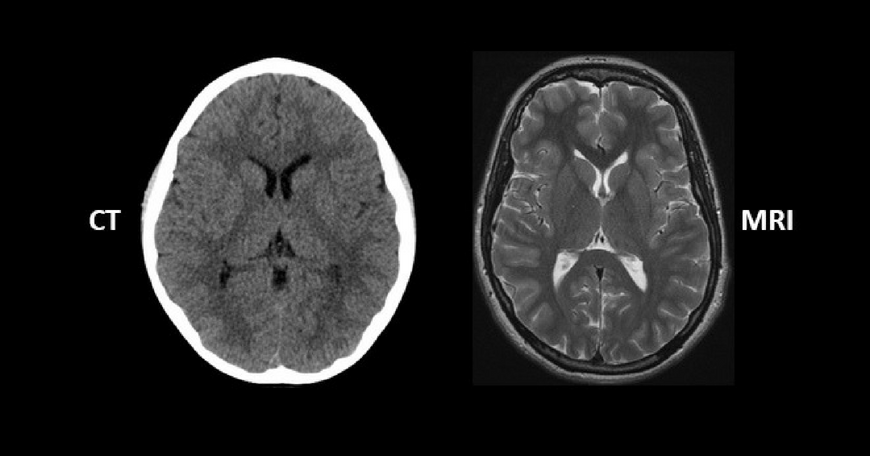

فرق سی تی اسکن و ام آر آی همیشه یکی از پرسشهای رایج بیماران و حتی پزشکان بوده است. تصور کنید نیاز دارید وضعیت داخلی بدن خود یا عزیزانتان را بررسی کنید، اما نمیدانید کدام روش مناسبتر است: سی تی اسکن یا ام آر آی؟ آیا هر دو یک کاربرد دارند یا هر کدام کاربرد خاص خود را دارند؟ انتخاب بین این دو روش تصویربرداری پیشرفته، بسته به نوع بررسی، سرعت تشخیص و دقت مورد نیاز متفاوت است.

انتخاب بین سی تی اسکن و ام آر آی اغلب بیماران را سردرگم میکند. سی تی اسکن سریع و مناسب استخوان و خونریزی است، در حالی که ام آر آی برای بررسی دقیق بافتهای نرم و ارگانهای داخلی بهترین گزینه است. جدول زیر تفاوت سی تی اسکن و ام آر آی را نشان میدهد.

با توجه به فرق سی تی اسکن و ام آر آی، انتخاب روش مناسب بستگی به هدف تشخیصی دارد: سی تی اسکن سریع و مناسب شرایط اورژانسی است، ام آر آی دقت بالایی در بافت نرم و جزئیات داخلی بدن ارائه میدهد.

سی تی اسکن یا CT Scan یکی از روشهای پیشرفته تصویربرداری پزشکی است که با استفاده از اشعه ایکس و پردازش کامپیوتری تصاویر مقطعی و دقیق از بدن تولید میکند. این تصاویر به پزشکان کمک میکنند تا ساختارهای داخلی بدن مانند استخوانها، ریهها، عروق و اعضای داخلی را از زوایای مختلف بررسی کنند. یکی از مهمترین مزایای سی تی اسکن، سرعت بالای آن است؛ به همین دلیل در شرایط اورژانسی مانند تصادفات یا خونریزیهای داخلی، معمولاً اولویت انتخاب پزشکان است. کاربردها و مزایای سی تی اسکن:

Hاین روش در بهترین مراکز سی تی اسکن تهران با اشعه ایکس انجام میشود و تکرار مکرر آن محدود است. این روش در بررسی بافتهای نرم مانند عضلات و برخی ارگانها دقت کمتری دارد. درک فرق سی تی اسکن و ام آر آی به پزشکان و بیماران کمک میکند تا بدانند چه زمانی استفاده از این روش سریع و کاربردی است.

ام آر آی چیست و چه کاربردی دارد؟

ام آر آی یا MRI یک روش تصویربرداری پیشرفته است که با استفاده از میدان مغناطیسی قوی و امواج رادیویی تصاویر سهبعدی و با جزئیات بالا از بدن ایجاد میکند. برخلاف سی تی اسکن، ام آر آی اشعه ایکس ندارد و برای اکثر بیماران کاملاً ایمن است. این ویژگی باعث شده تا ام آر آی برای بررسی طولانیمدت یا تکراری بیماران بسیار مناسب باشد، به ویژه زمانی که نیاز به مشاهده دقیق بافتهای نرم وجود دارد. کاربردها و مزایای ام آر آی:

ام آر آی زمان طولانیتری نسبت به سی تی اسکن دارد و هزینه بالاتری دارد. افرادی که ایمپلنت فلزی یا دستگاه ضربانساز قلب دارند، ممکن است نتوانند از آن استفاده کنند. آشنایی با فرق سی تی اسکن و ام آر آی کمک میکند بیماران بدانند چه زمانی نیاز به تصویربرداری با جزئیات بالای بافت نرم دارند و چه زمانی روش سریعتر و سادهتر مناسب است.

انتخاب بین سی تی اسکن و ام آر آی بستگی به نوع مشکل پزشکی، ناحیه مورد بررسی و شرایط بیمار دارد. برای مثال، در شرایط اورژانسی مانند تصادفات یا خونریزیهای داخلی، سی تی اسکن به دلیل سرعت بالا و دقت در بررسی ساختارهای سخت، انتخاب مناسبی است. در مقابل، برای بررسی دقیق بافتهای نرم مانند مغز، نخاع یا عضلات، ام آر آی به دلیل دقت بالا و عدم استفاده از اشعه ایکس، مناسبتر است. شناخت فرق سی تی اسکن و ام آر آی به بیماران و پزشکان کمک میکند تا تصمیمی آگاهانه برای تشخیص سریع یا دقیقترین بررسی اتخاذ کنند.